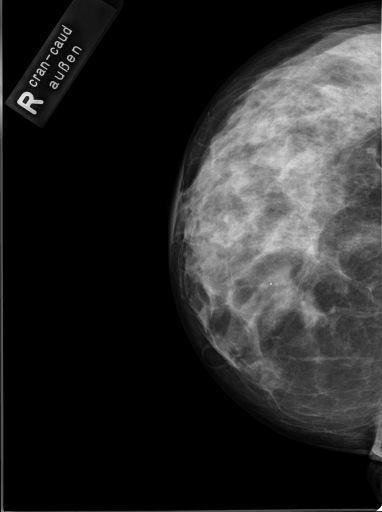

Image Dataset – The Image Retrieval in Medical Applications (IRMA) 2009 database is a collection of 14,410 x-ray images that have been randomly collected from daily routine work at the Department of Diagnostic Radiology of the RWTH Aachen University (Fig. 2). The downscaled images were collected from different ages, genders, view positions, and pathologies [33]. Each image in the dataset has an IRMA code. According to these codes, 193 classes are defined according to 2008 IRMA codes. The IRMA code comprises four axes with three to four positions each: 1) the technical code (T) (modality), 2) the directional code (D) (body orientations), 3) the anatomical code (A) (body region), and 4) the biological code (B) (the biological system examined). The complete IRMA code consists of 13 characters TTTT-DDD-AAA-BBB, with each character in . As many as 12,677 images are separated for training. The remaining 1,733 images are used as test data. In this project, the IRMA 2009 dataset has been used with specified 2008 IRMA labels (consisting of 193 classes) for retrieval purposes. Otherwise, same dataset is utilized with general 2005 IRMA labels (consisting of 57 classes) for classification purpose. 2005 IRMA labels are more general than 2008 IRMA labels because it has been made of 6 characters from top of hierarchical classes, TT-D-AA-B. In 2009 dataset, each image can not have been coded according to 2005 IRMA coding regularity. A total number of 12,631 images from training set and 1,639 images from testing set have 2005 IRMA codes. For this reason, SVM classification is implemented on corresponding images.